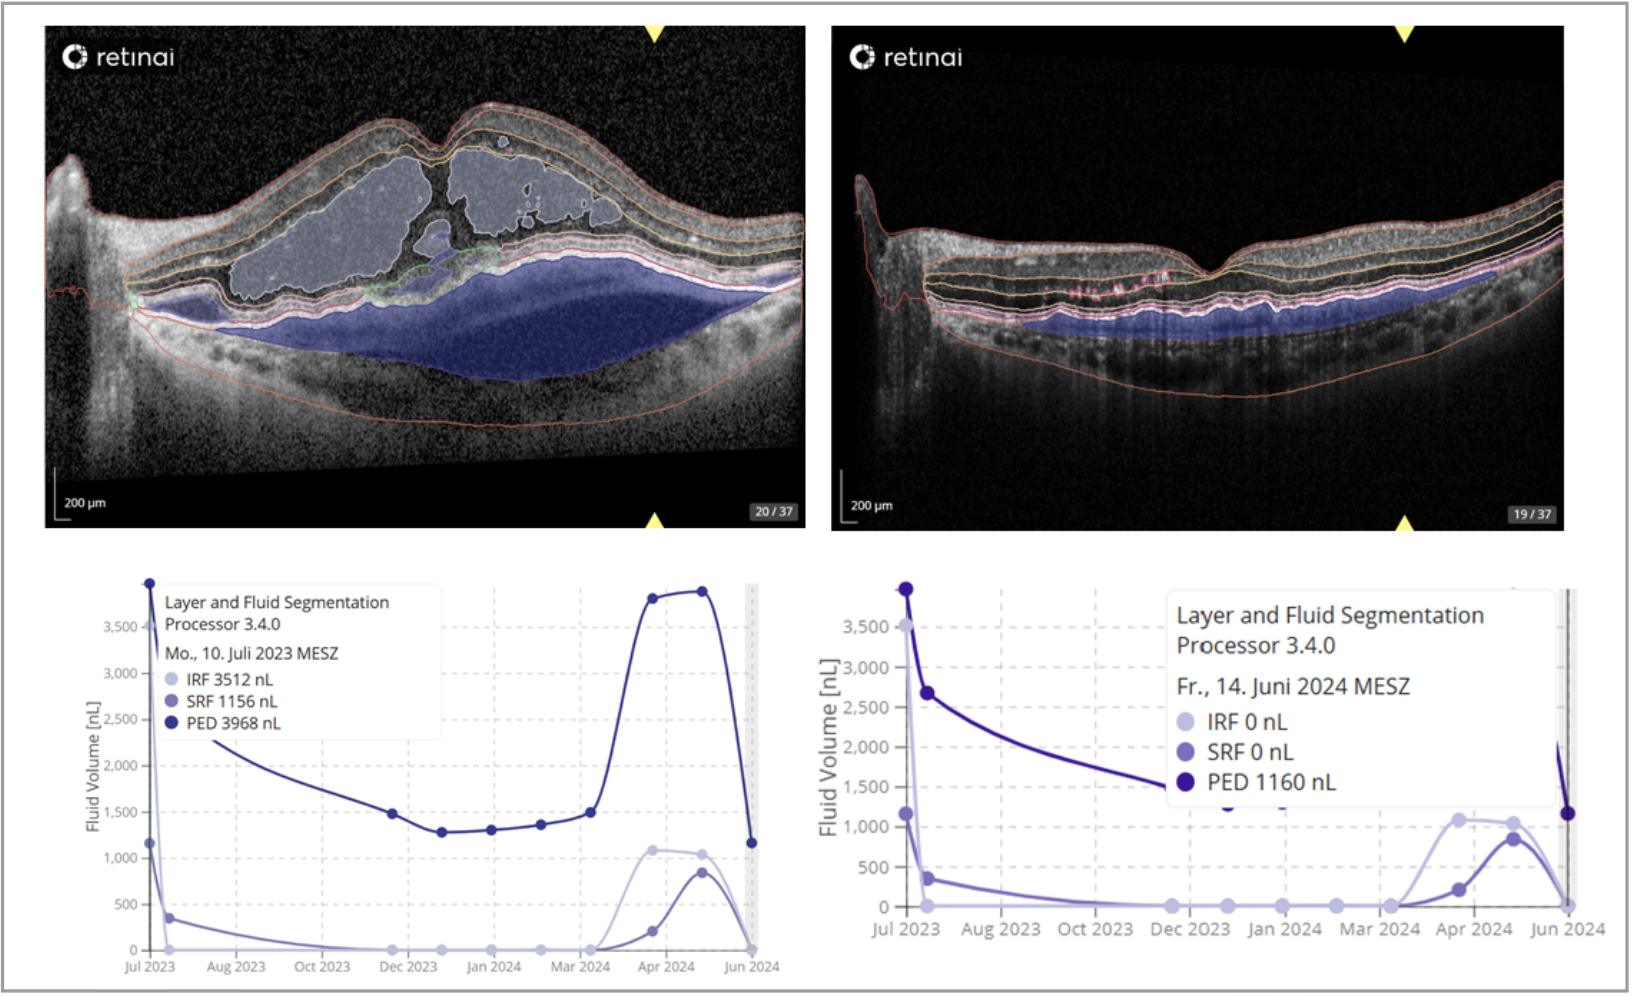

| Figure 1. AI-based OCT layer and fluid segmentation in neovascular AMD. Representative OCT B-scans (top) with automated detection of intraretinal fluid (IRF), subretinal fluid (SRF) and pigment epithelial detachment (PED) using an AI-based segmentation algorithm (RetinAI). Quantitative analysis of fluid compartments (bottom) shows dynamic changes in IRF, SRF and PED volumes over time, illustrating treatment response and disease activity monitoring. |

• AI for detection and quantification of biomarkers. Several AI systems are now commercially available to detect, classify and quantify fluid biomarkers (intraretinal, subretinal and sub-RPE fluid) in OCT scans of patients with neovascular AMD. These include the Notal OCT Analyzer (USA), RetinAI Discovery (Switzerland) and RetInSight Fluid Monitor (Austria). Most are based on standard deep learning (DL) architectures and have been validated against humans, showing comparable performance. Typically cloud-based, these systems require clinicians to upload OCT scans via a web interface.

First and foremost, complex treatment regimens (e.g., SRF-tolerant protocols) require analyzing fluid stability over time, including precise measurement of its volume and/or height—metrics that, in practice, can only be reliably obtained with AI-assisted analytics. However, clinical evidence comparing AI-based approaches to current standards of care remains limited, which may explain the slow adoption of AI in routine practice. A large volume of intraretinal or subretinal fluid is typically considered a sign of disease activity, while complete absence of fluid usually supports a decision of inactivity. However, intermediate volumes—often in the range of just a few nanoliters—don’t always translate directly into activity assessments by the treating specialist. This illustrates why precise quantification through AI may help standardize interpretation and reduce subjectivity in clinical decision-making.